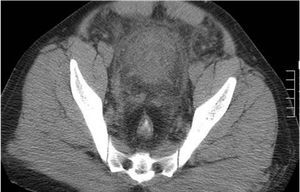

A 40-year-old male presented at the ER with chest discomfort and tacchypnia. No abnormal radiological findings could be detected on the chest X-ray. On examination ischemic changes on the right lower limb, with ECG changes were noted.